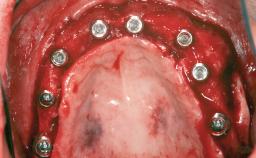

# of Implants 1

Type of Implants Two-Piece

Bone Augmentation Staged|Vertical

Augmentation Materials Autogenous chips|Membrane